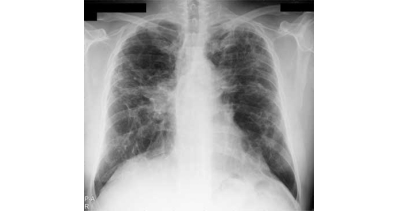

Gruźlica jest chorobą zakaźną – wywoływaną przez bakterię – prątek gruźlicy. Źródłem zakażenia jest najczęściej chory na gruźlicę – prątkujący. Choroba rozwija się gdy nastąpi osłabienie sił obronnych organizmu. Program adresowany jest do osób powyżej 18. roku życia, które nie miały w dotychczasowym...